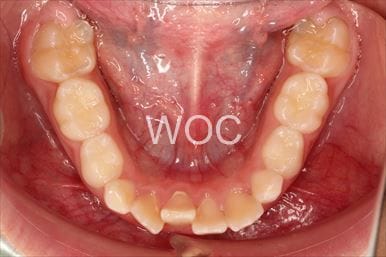

治療後1

-

治療後2

-

治療後3

-

治療後4

-

治療後5

- 年齢:20歳女性

- 主訴:出っ歯が気になる

- 基本矯正料金:120万円

- 治療期間:1年7ヶ月

- 抜歯部位:上顎両側第一小臼歯